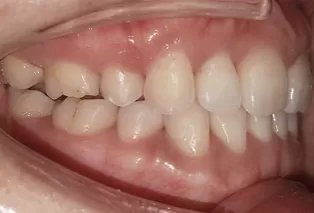

Intraoral photos